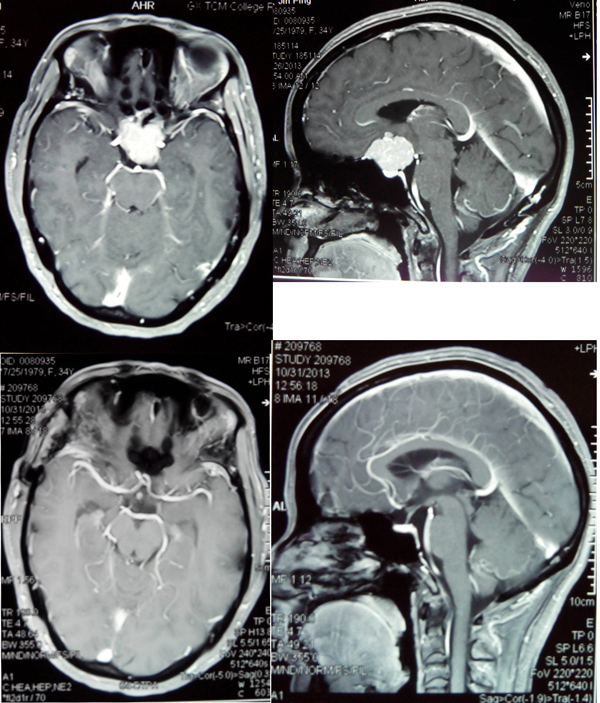

今年6月份视力下降到半米外都看不清手指数,李老师再不敢大意,到医院检查发现是脑部长了肿瘤。由于肿瘤长在脑部关键部位,周围布满神经和血管,手术难度极大,当地医院介于技术条件有限便建议其到我院就诊。

李老师进入我院时检查显示,左侧视力仅有1米指数,右侧视力仅有0.5米指数,佩戴眼镜后左侧视力0.1,右侧视力0.25。视力已接近失明,如果不及时治疗,最终将真正失明。

神经外科范学政主任和李亚平等医生认真分析了李老师的病情:肿瘤长在颅内鞍区,只能手术治疗,但是肿瘤与颈动脉和视神经的距离只有几毫米,手术稍有不慎就会损伤颈动脉引起大出血。如果损伤视神经则会失明,甚至有可能引起肿瘤周围的垂体等重要神经组织损伤,导致尿崩电解质混乱,昏迷甚至成为植物人。

带着李老师的重托,范主任认真制定了严密的手术方案,于7月31日主刀为其手术。范主任在显微镜下小心翼翼地操作,经过几个小时终于将肿瘤完全切除,而且没有损伤肿瘤周围的血管和神经,未出现任何并发症。术后2个月,李老师的视力已经明显恢复,再一次回到心爱的工作岗位。

上图为治疗前肿瘤,下图为治疗后肿瘤消失